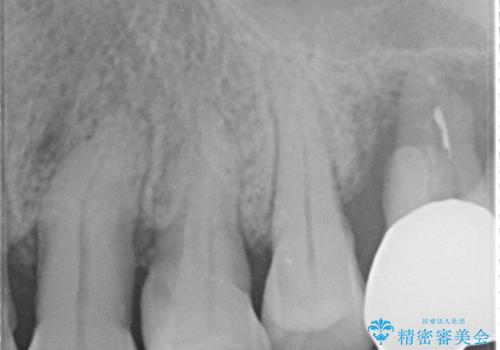

- 夜間のくいしばり、はぎしりが激しく全体的な歯周病が進行し、治療を希望され来院されました。

歯周ポケットの徹底的な除去を行なったのち、歯の揺れを抑え、過大な力がかからぬよう連結クラウン(歯周補綴)を行い強大な力に対抗します。

夜間の歯ぎしりにはナイトガードを用いて大きな力がかからないような対処が必要です。